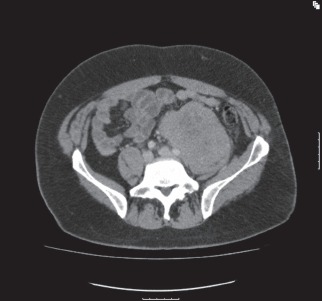

The retroperitoneum can host a wide spectrum of pathologies, including a variety of rare benign tumours and malignant neoplasms that can be either primary or metastatic lesions. Malignant tumours of the retroperitoneum occur four times more frequently than benign lesions.1 Sarcomas comprise a third of retroperitoneal tumours. Soft tissue sarcomas are rare tumours, with retroperitoneal sarcomas expected to compose approximately 15% of the 2,000 cases of soft tissue sarcomas anticipated in England and Wales each year.2 In the UK there are estimated to be between 250 and 300 new diagnoses of retroperitoneal sarcoma (RPS) each year. The retroperitoneum represents the second most common site of origin of malignant mesenchymal tumours after the lower extremities.3 Retroperitoneal tumours present several therapeutic challenges because of their relative late presentation and anatomical location (Fig 1).4 This review highlights the presentation, evaluation and initial management of patients presenting with retroperitoneal tumours and the surgical management of RPS.

Figure 1.

CT of a 35-year-old male showing a large left-sided retroperitoneal dedifferentiated liposarcoma. The tumour weighed 15kg at resection.